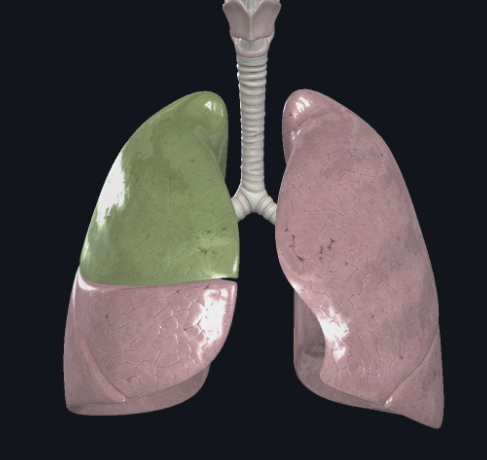

What structure is this?

Diaphragm

Cardiac Notch

What structure is this?

Superior Lobe of the right lung

What structure is this?

Middle lobe of the right lung

What structure is this?

Inferior lobe of the right lung

What structure is this?

Left lung

What structure is this?

Right lung